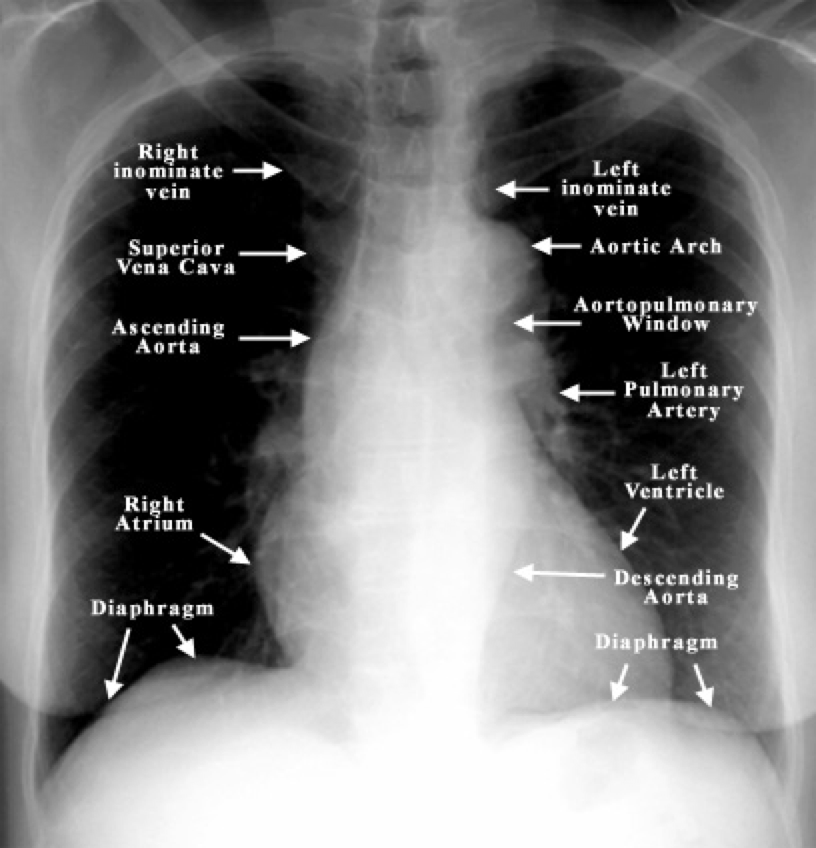

- Heart:

- Normal size = <50% chest width (PA view)

- Cardiomegaly may indicate heart failure, LV/RV hypertrophy, or pericardial effusion

- Mediastinum:

- Evaluate borders of aorta, heart, diaphragm

- Trachea:

- Should be midline

- Deviation may suggest tension pneumothorax, collapse, or large effusion

- Carina:

- Bifurcation of bronchi

- Widened/distorted → consider malignancy

- Diaphragm:

- Right dome higher (due to liver)

- Blunted costophrenic angles = pleural effusion

Hilar Region

- Should be symmetrical

- Enlargement = dilated vessels or lymphadenopathy

Heart Borders

- Well defined margins

- May be obscured by adjacent pathology (e.g. pneumonia)

Cardiothoracic Ratio

- Heart width >50% chest width = cardiomegaly